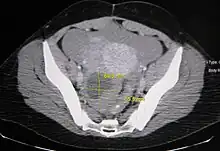

Ovarian cysts are usually diagnosed by ultrasound, CT scan, or MRI, and correlated with clinical presentation and endocrinologic tests as appropriate.[10]

Follow-up imaging in women of reproductive age for incidentally discovered simple cysts on ultrasound is not needed until 5 cm, as these are usually normal ovarian follicles. Simple cysts 5 to 7 cm in premenopausal females should be followed yearly. Simple cysts larger than 7 cm require further imaging with MRI or surgical assessment. Because they are large, they cannot be reliably assessed by ultrasound alone; it can be difficult to see posterior wall soft tissue nodularity or thickened septation due to limited ultrasound beam penetrance at this size and depth. For the corpus luteum, a dominant ovulating follicle that typically appears as a cyst with circumferentially thickened walls and crenulated inner margins, follow up is not needed if the cyst is less than 3 cm in diameter. In postmenopausal patients, any simple cyst greater than 1 cm but less than 7 cm needs yearly follow-up, while those greater than 7 cm need MRI or surgical evaluation, similar to reproductive age females.[11]

For multiloculate cysts with thin septation less than 3 mm, surgical evaluation is recommended. The presence of multiloculation suggests a neoplasm, although the thin septation implies that the neoplasm is benign. For any thickened septation, nodularity, vascular flow on color doppler, or growth over several ultrasounds, surgical removal may be considered due to concern of cancer.[11]